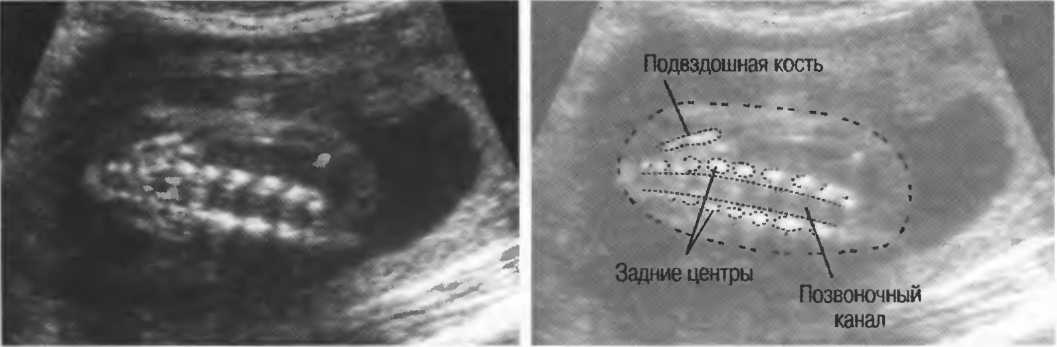

Рис.5. Два поперечных среза плода, демонстрирующих тень от позвоночника плода. Аналогичная тень от ребер может частично закрывать почки или печень. Изменяя угол наклона датчика, можно изменить положение тени таким образом, чтобы подлежащие ткани были видны отчетливо.